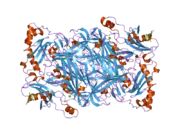

Structure

VAP-1 is a type 1 membrane-bound glycoprotein that has a distal adhesion domain and an enzymatically active amine oxidase site outside of the membrane.[6][7] The AOC3 gene is mapped onto 17q21 and has an exon count of 6.[5]

Amine oxidases are a family of enzymes that catalyze the oxidation of various endogenous amines, including histamine or dopamine. VAP-1 constitutes the copper dependent class of amine oxidases, such as lysyl oxidase or lysine demethylase, and is one of the four known in humans. The other class is flavin dependent such as monoamine oxidase (MAO) A and B.[5][8] VAP-1, in particular, catalyzes the oxidative conversion of primary amines (methylamine and aminoacetone) to aldehydes (formaldehyde and methylglyoxal) ammonium and hydrogen peroxide in the presence of copper and quinone cofactor.[8][9][10]